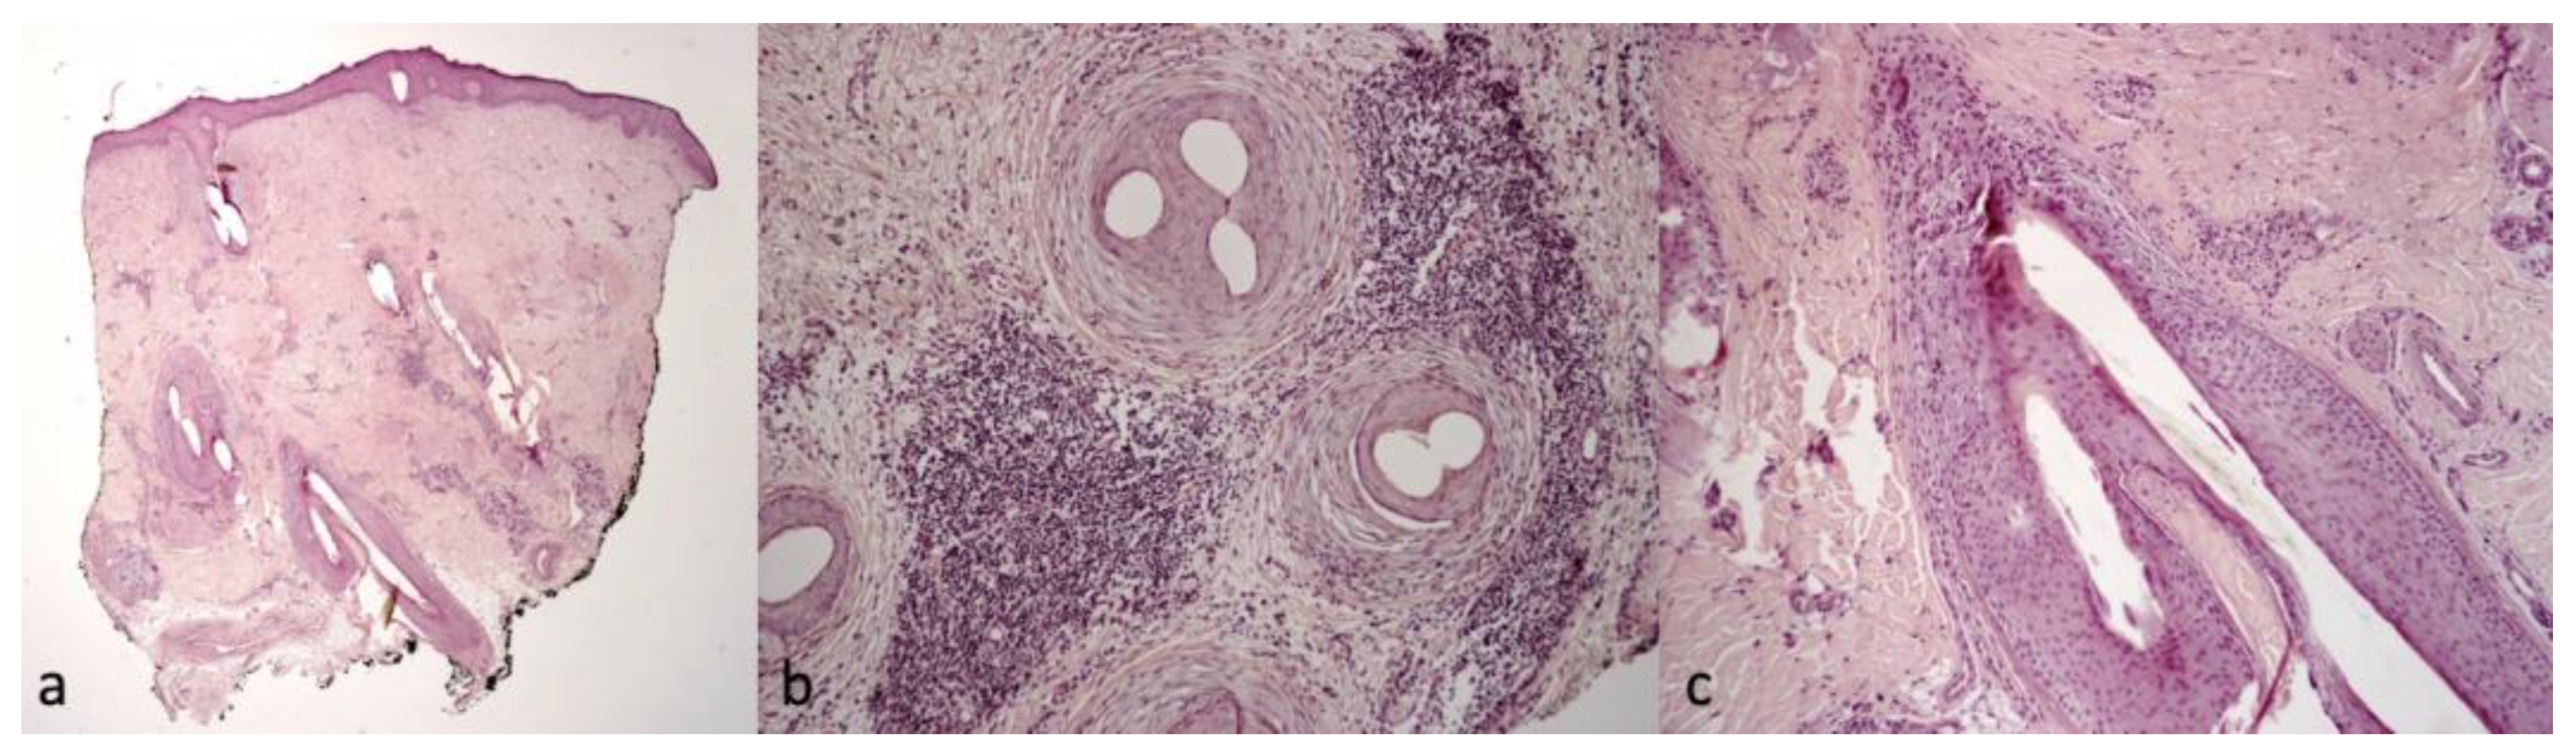

| 1 | 25/F | UCMD | COL6A1 c.850G>A | Keloids, follicular hyperkeratosis | Severe itching | White-yellow scales | Erythema, twisted red loop vessels, and yellow interfollicular scales | Dilated vessels in the dermis; parakeratosis, focal absence of granular layer in the epidermis, and neutrophilic infiltrate in the papillary dermis mantles (sebaceous structures) |

| 2 | 29/F | UCMD | COL6A1 c.958-2A>G | Face and neck hirsutism, keloids | Severe itching | Small cicatricial areas on vertex | Tufted hair, absence of follicular ostia in cicatricial area, and dilated elongated vessels | Dense diffuse suppurative, mixed infiltrate in the dermis. “Tufted folliculitis” and intraepidermal pustules |

| 3 | 24/F | UCMD | COL6A2 homozygous c.348dup | Keloids | Mild itching | Cicatricial patch on vertex | Severe erythema, dilated vessels, yellow scales, tufted hair, perifollicular pustules, and cicatricial areas with absence of follicular ostia | Superficial perivascular and perifollicular infiltrates of lymphocytes and neutrophils |

| 4 | 37/F | UCMD | COL6A2 c.875G>T | Keloids, follicular hyperkeratosis | Severe itching | Fine scaling | Perifollicular scales and erythema | Superficial perivascular and perifollicular infiltrates of lymphocytes and neutrophils; collection of neutrophils within infundibula |

| 5 | 24/M | UCMD | COL6A1 c.930+189C>T | Keloids, follicular hyperkeratosis | Severe itching | Hair thinning | Different hair diameters, erythema, dilated vessels, and yellow scales | Superficial perivascular and perifollicular infiltrates of lymphocytes and neutrophils |